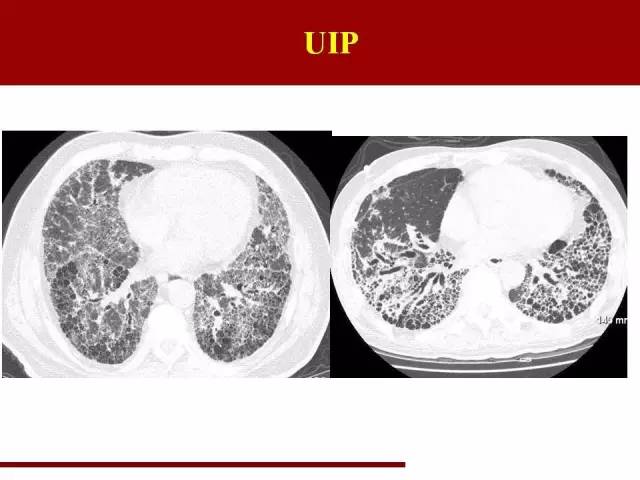

红字是主要特点,蓝字是必须排除的要点

影像特点大家应该都很熟悉,但是少有人注意需要排除的条件

这点在诊断的过程中必须注意

双肺中下肺野胸膜下分布、网格状阴影多于磨玻璃阴影,终末期可以有蜂窝肺形成,伴有牵拉性支气管扩张